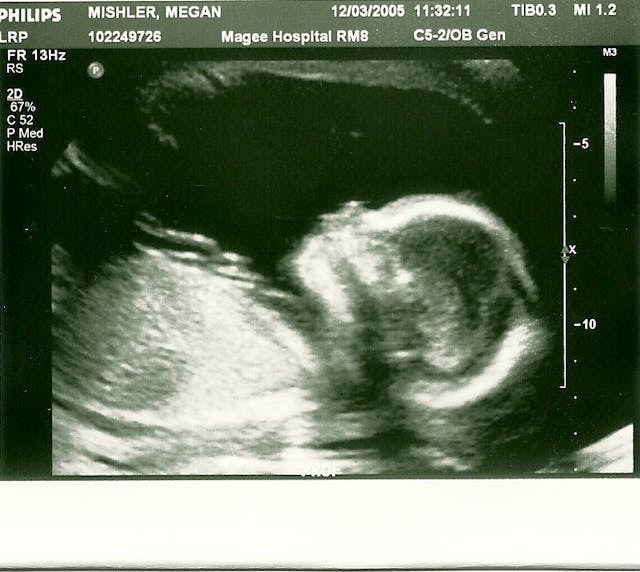

The thought of giving her up was tearing me apart but the pregnancy did not proceed normally. I ended up in the hospital for weeks, on bed rest, trying to prevent a very premature birth. I had the chance to watch my little girl grow via ultrasound: I saw her heart beating, I saw her sucking her thumb and playing with her toes, and I saw her hair like a halo around her head.

Ironically, I made it to full term before tragedy struck in an unexpected way. My daughter Lillian Mary was stillborn because of a cord accident. I would have given anything, I would still give anything, for her to open her eyes or grasp my finger, even for a moment. But I had the chance to love her and know her in the womb. If I had aborted her to stay in school, like some of my friends recommended, I would have missed having her in my life. I would never have known how beautiful she was, or held her perfect body, wrapped in hospital blankets, in my arms. I could never have seen her face in my nieces.

With my son Gaven Joseph, I was not so fortunate. The pregnancy was rough from the beginning. I went to a high risk clinic in Pittsburgh and the doctors and social workers there strongly suggested that I ought to abort, considering my psychosocial risk factors in addition to the physical risk factors. The baby’s father was an alcoholic, an addict, and abusive, and the high risk clinic knew it. I was working with a social worker on plans to safely leave him once my son was born. Physically, there were things that required monitoring but as the pregnancy progressed, they appeared to resolve, until I reached 22 weeks and became extremely sick with a respiratory infection.

I was hospitalized in Pittsburgh and I had finally started improving. I had just moved out of intensive care when I felt a terrible pain, and saw something even worse: blood. My nurse called the doctor on call on my floor. After performing an urgent bedside ultrasound, they determined two things: my son was alive, but I had a placental abruption which was causing the bleeding. The doctor on the unit told me not to panic, that the tear was minor, and that the OB/GYN doctors saw these all the time and could handle it.

My parents had arrived at the hospital later that morning and were there to tell me it was time to allow the doctors to take my son via an emergency D&E, or even a hysterectomy to stop the bleeding, to try to save my life. At the last ultrasound done to check on the placental abruption, my son was still alive. But things had gotten much worse and I didn’t know if he was still alive or not, and I wasn’t in a great state in being able to make decisions. I didn’t want to live at my son’s expense; in fact, at that point I wanted to die with him rather than be responsible for his death.